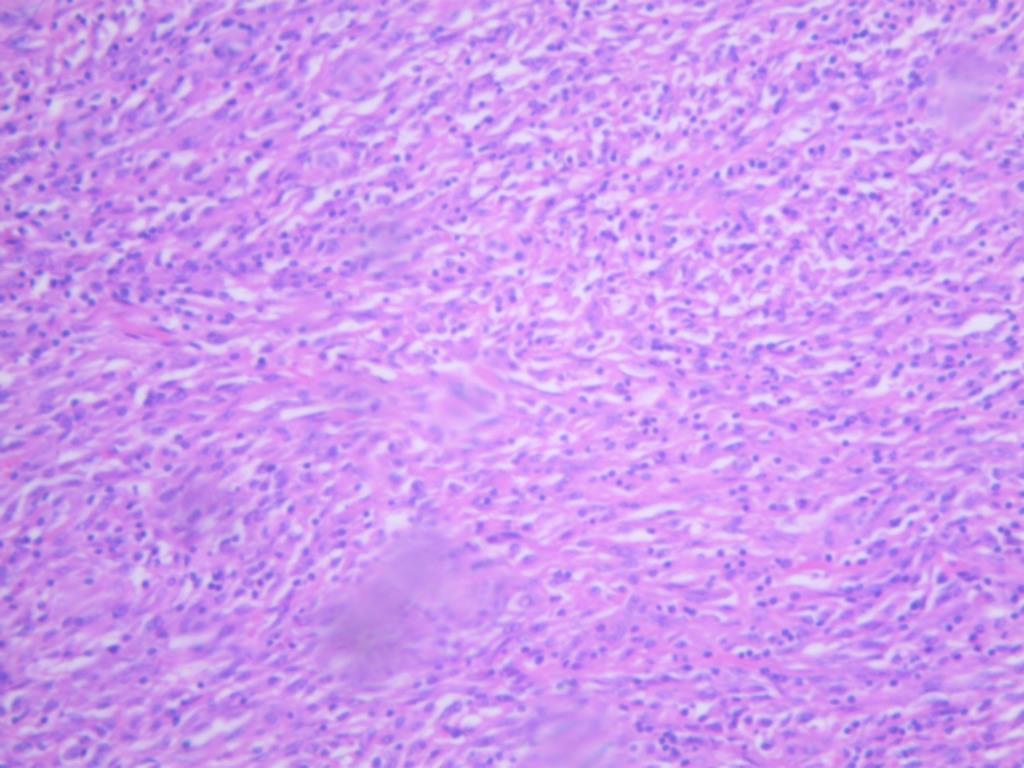

病理:< “左前臂肿物”>恶性肿瘤,结合HE及免疫组化结果,首先考虑滑膜肉瘤。

超声检查左前臂下段近腕关节处肌层内可见一个肿块图像,深面达尺桡骨之间,大小约52×40×33mm,形状呈分叶状,边界尚清楚,内部为中等稍低回声,分布不均质,后方回声无变化,彩色多普勒显示:肿块周边及内部可见点条状血流信号。

超声提示:左前臂下段近腕关节处肌层内实质性占位病变,性质待查,请结合其他影像学检查。